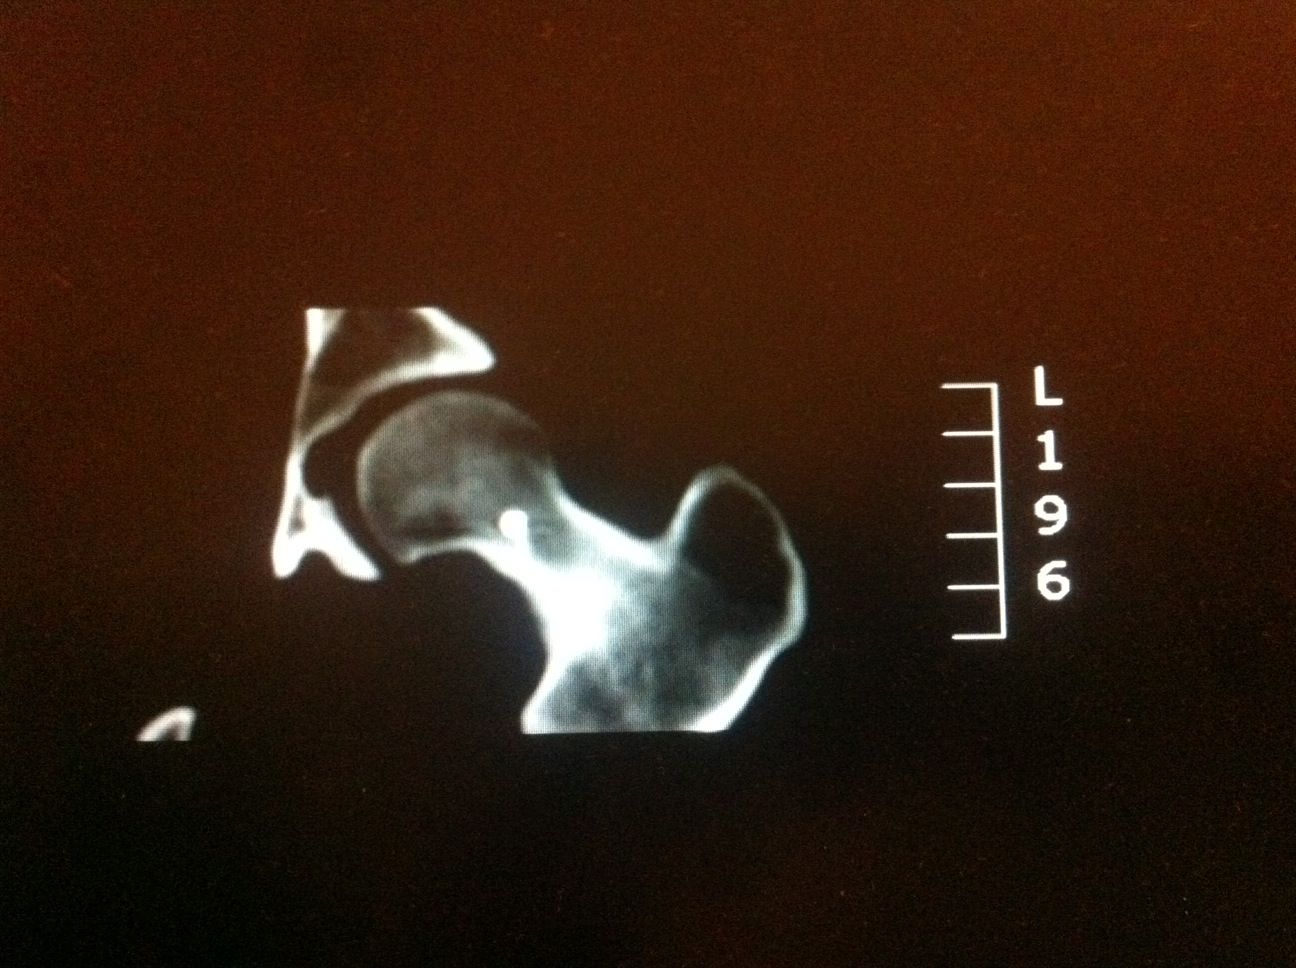

L’Examen est centré sur la région d’intérêt par Acquisition hélicoïdale de Coupes de 1 à 2mm jointives

Le scanner permet de repérer :

Le Nidus = hypodensité à contours nets associé à une hyperdensité calcique linéaire centro-tumorale correspondant à la vascularisation centrale. Une zone hypodense osseuse linéaire au niveau perilésionnel en regard de la condensation est assez spécifique. L’Ostéocondensation périphérique est homogène et peut provoquer une réaction périoste.